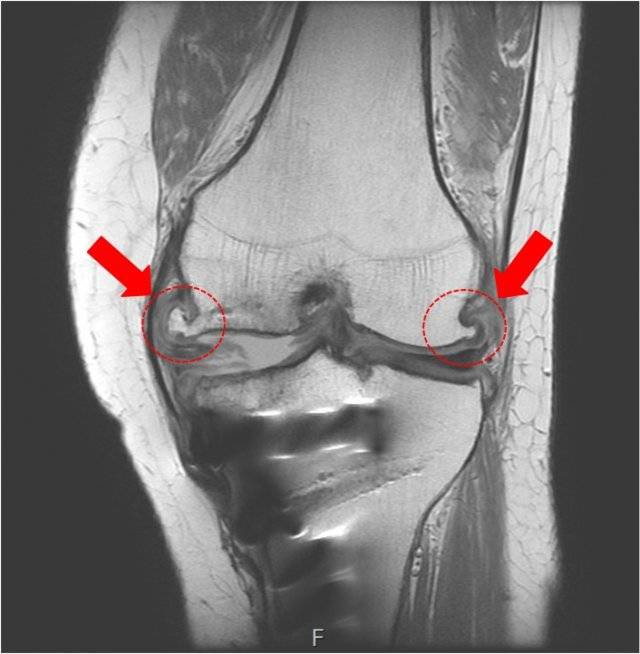

송 원장은 “운동에 중요한 역할을 하는 관절 건강도 살핀 뒤 운동해야 100세까지 즐길 수 있다”고 말했다. 무릎 및 발목 MRI(자기공명촬영)를 찍어보고 연골, 인대, 건 등에 문제가 있는지 살펴보고 몸 상태(체중, 키, 자세 등)에 따라 맞은 운동을 해야 부상을 막고 운동을 즐길 수 있다는 얘기다.